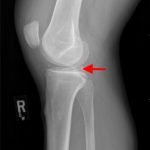

Radiographs of the knee showed multiple radio-dense lines paralleling the articular surface (see red arrows) consistent with calcium pyrophosphate crystal deposition within the joint often seen in calcium pyrophosphate disease (CPPD) also known as pseudogout.

Patients commonly present to the emergency department with non-traumatic joint pain. Arthrocentesis is an important diagnostic tool to evaluate for septic arthritis, gout, or pseudogout. Arthrocentesis can demonstrate crystals or abnormal cell count, gram stain, and culture.[1] In the evaluation of joint pain, plain films are usually obtained to evaluate for fracture, dislocation, effusion, or secondary signs of infection. In this case the classic x-ray supported the diagnosis of CPPD.2 The patient was found to have positively birefringent rhomboid shaped crystals consistent with pseudogout on arthrocentesis. Gram stain and culture were both negative. The patient was discharged with NSAIDs and had significant improvement in symptoms upon follow up with primary care physician in 3 days.